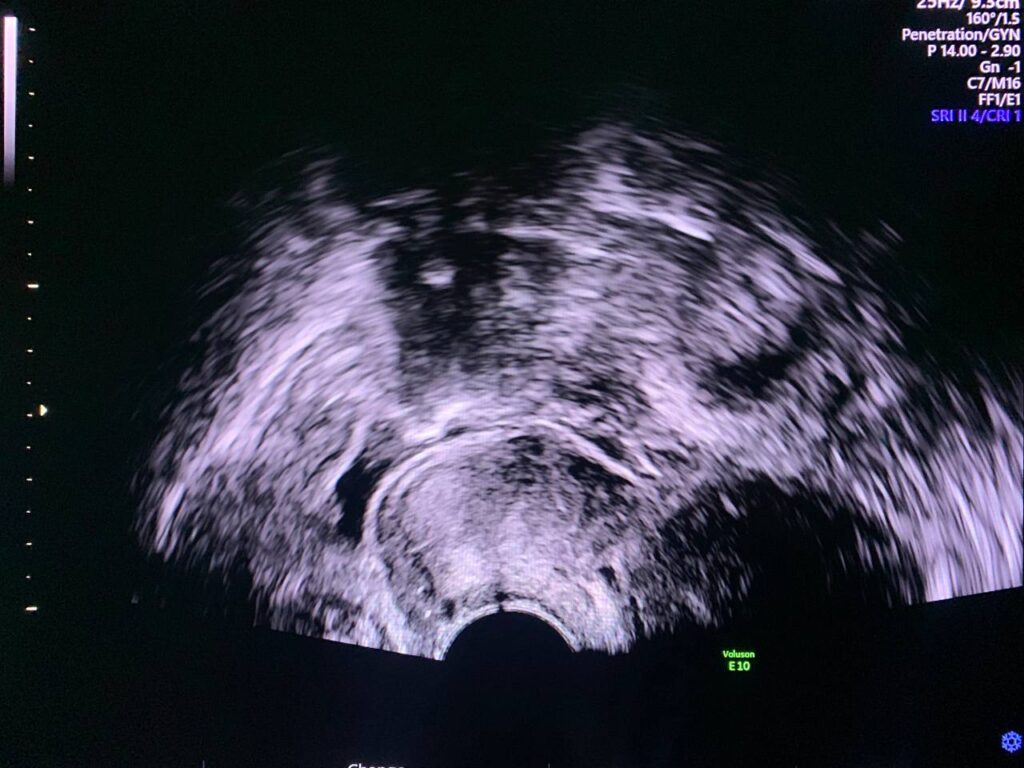

Both ovaries are enlarged in size, with increase stromal echogenicity, follicles (more than 30 in number in each ovary), their sizes less than 5mm, in favors of polycystic like ovaries, should be correlated with clinical picture & hormonal assay